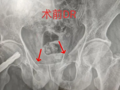

2025-08-28 【技术聚焦】我院外二科成功实施一例微创通道螺钉治疗骨盆骨折

2025-08-28 【技术聚焦】我院外二科团队成功实施一例联合前后双微创入路的复杂髋臼骨折内…